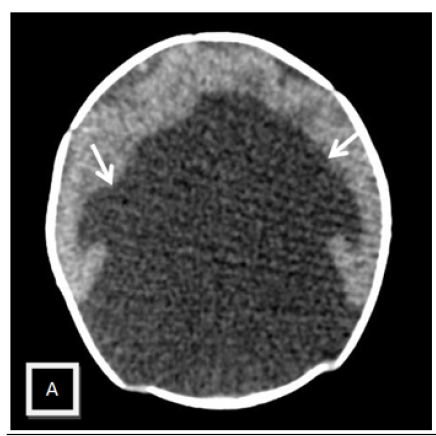

Holoprosencephaly Alobar: Contribution of Cerebral CT Scan in a Case Report

Khadija Laasri, Siham EL Haddad, Manal Jidal, Nazik Allali and Latifa Chat. 15(5): 53-56.